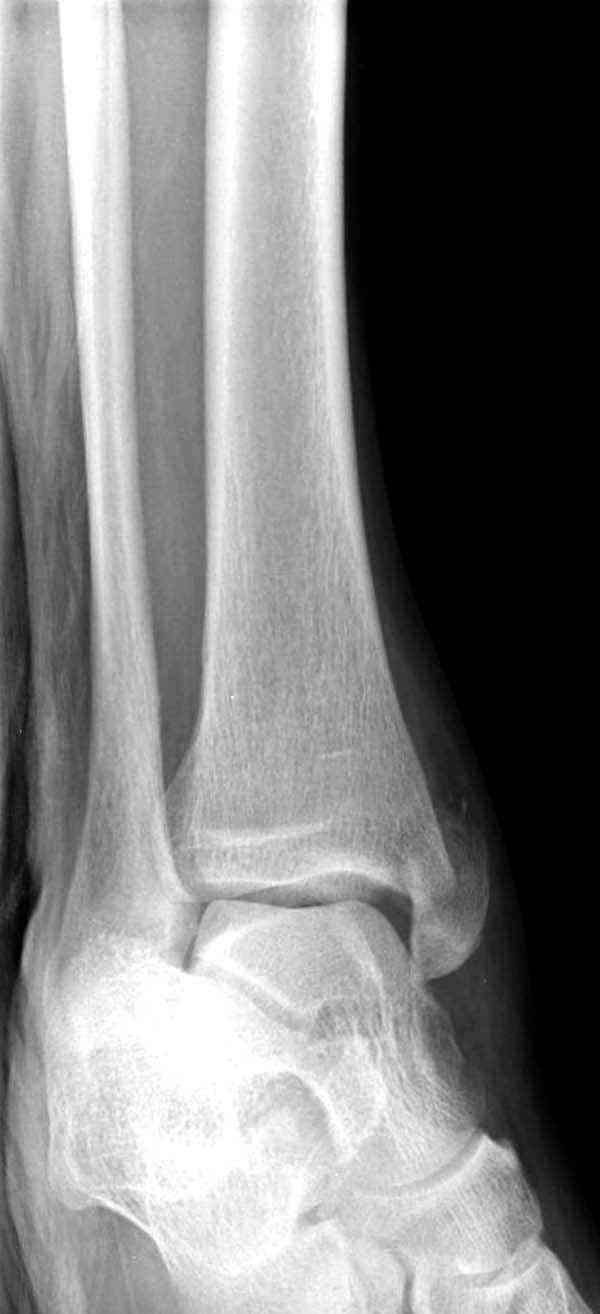

Внутренняя лодыжка

Вложение не в текстовом формате было извлечено…

Имя     : 4 Med mal fx Hook plate.JPG